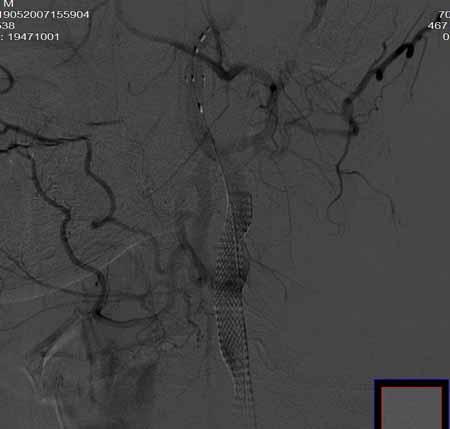

男,60岁。

腹主动脉、颈总动脉、颈内动脉狭窄支架置入术,最少放了三个支架吧,得十几万吧。

颈总动脉支架置入术。

指针宽了些

wallstent9*50可以全部覆盖,可以节约些

当然楼住的选择无可指责